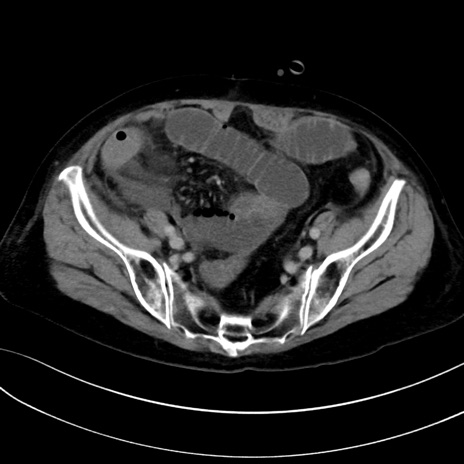

症例13 CT(横断像)1日半後